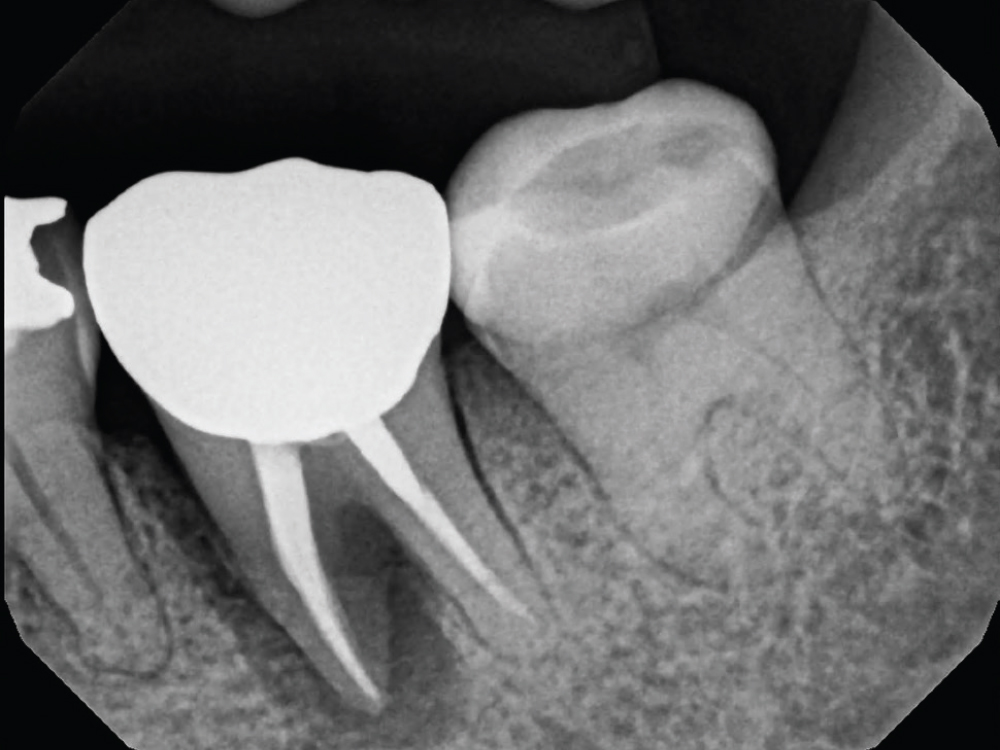

In-office milling is a quickly evolving option for the modern dental practice. With the introduction of a same-day screw-retained option, BruxZir® NOW SRC milling blocks, there’s even more opportunity for optimizing single-unit restoration workflows. In this case study, I’ll demonstrate how this product can be used as part of an efficient workflow for tooth replacement in the posterior. When combined with guided surgery and in-office crown design, this procedure offers reliable results while saving money and significantly cutting down on chair time for dentists.